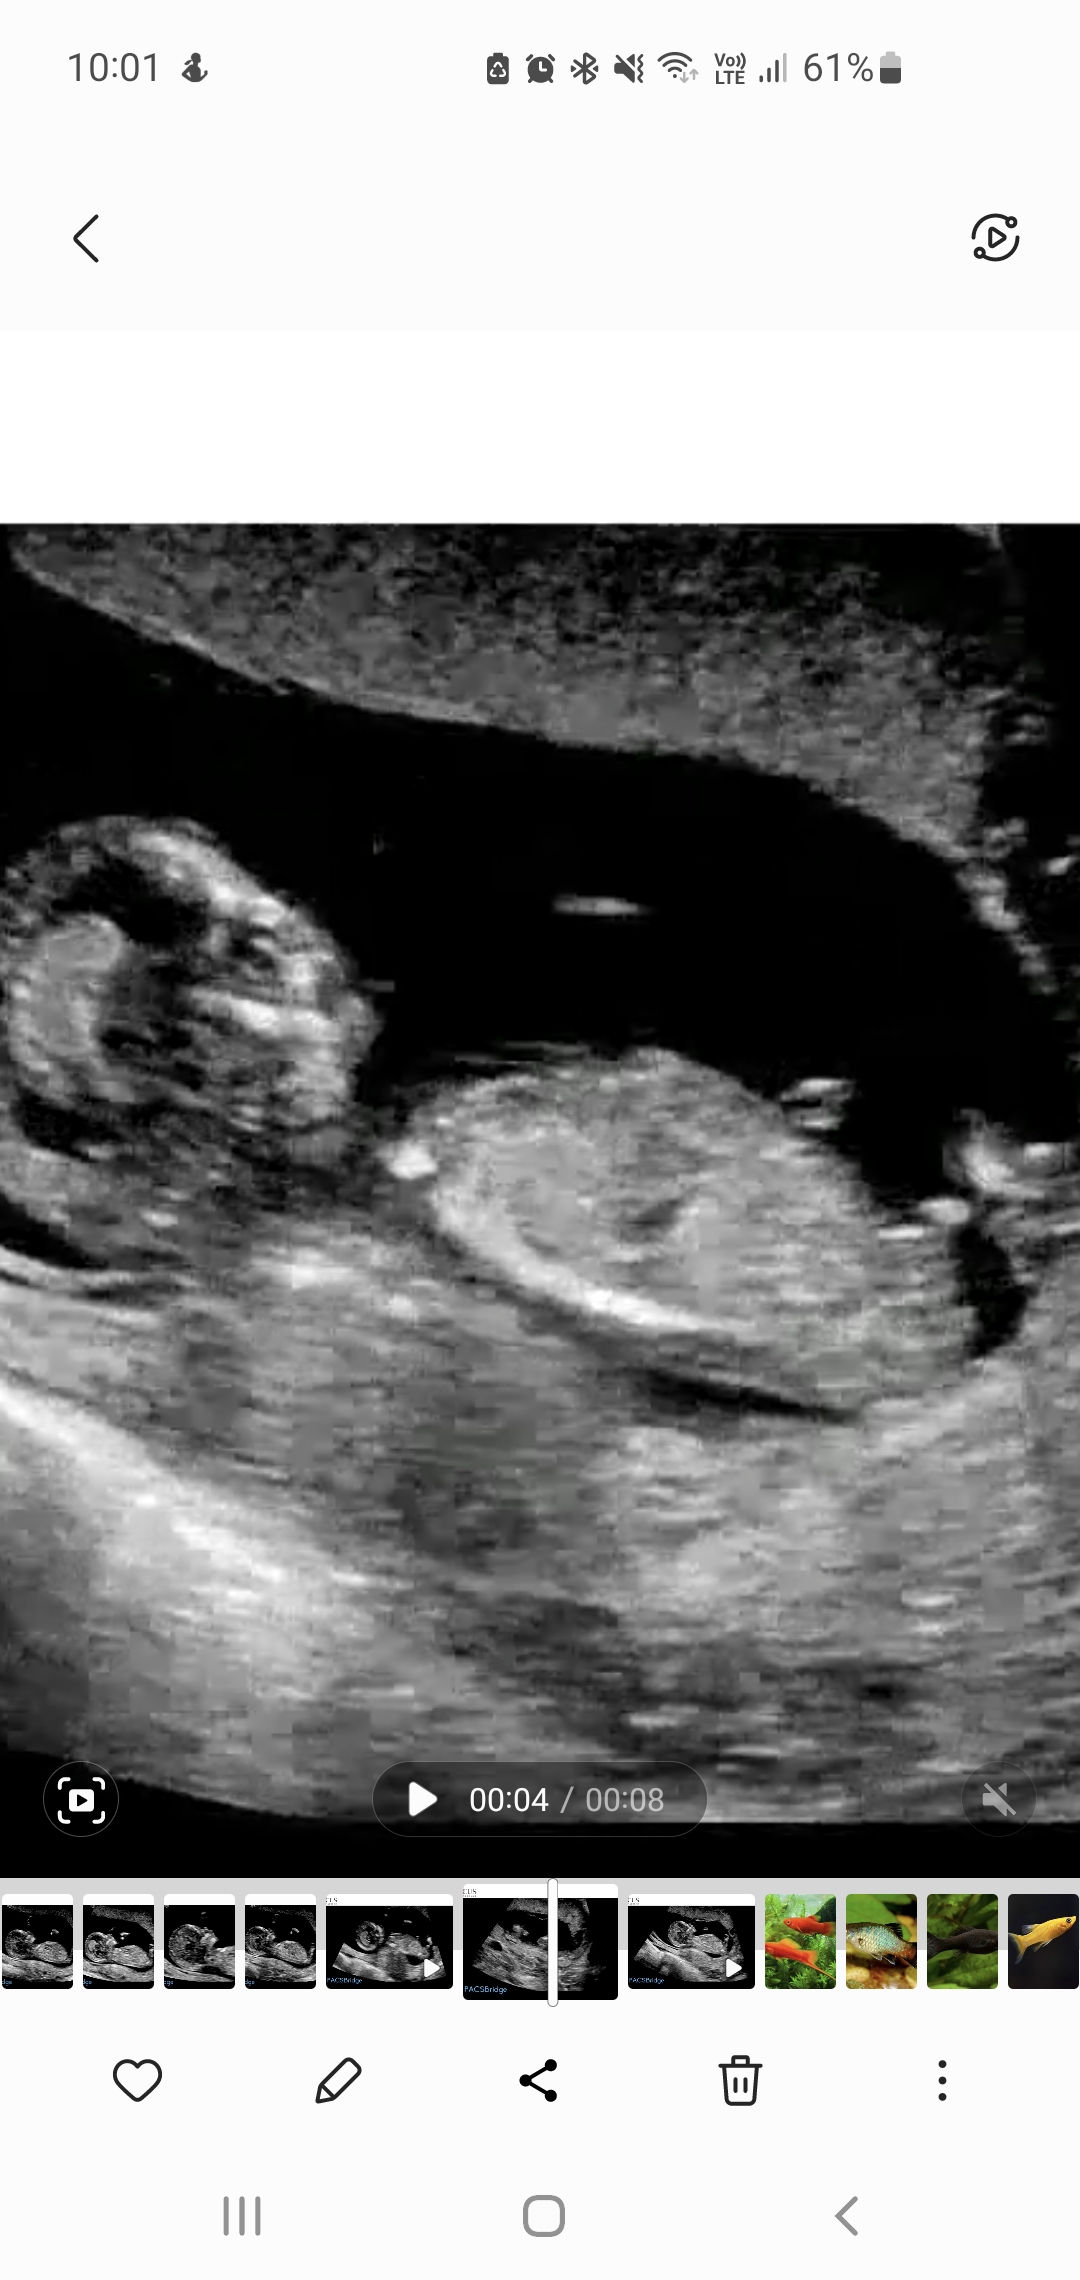

5th baby nub opinions please! 13th week

I swayed pink for a sister for my dd so I'll be honest I'm looking for hope this is a girl. So far only had boy comments elsewhere although some of the mods are 'maybe' boy, not 99%.

Atomic you've seen one of my pics in my swaying thread already but these are some more I've got from pausing the video (every micro second!). Baby was not in perfect sagittal position. I did during the scan see flashes of a long white, flat nub but she didn't capture it. She was trying to image the legs for nicer pics!

The skull/face reminds me of DDs scans but I've dreamt this bub is a boy which also happened just before I found out DS3 was a boy.

Gestation is 12+6 by OPKs & BBT, 13+5 by CRL.Attachment 43684Attachment 43685Attachment 43686Attachment 43687Attachment 43688